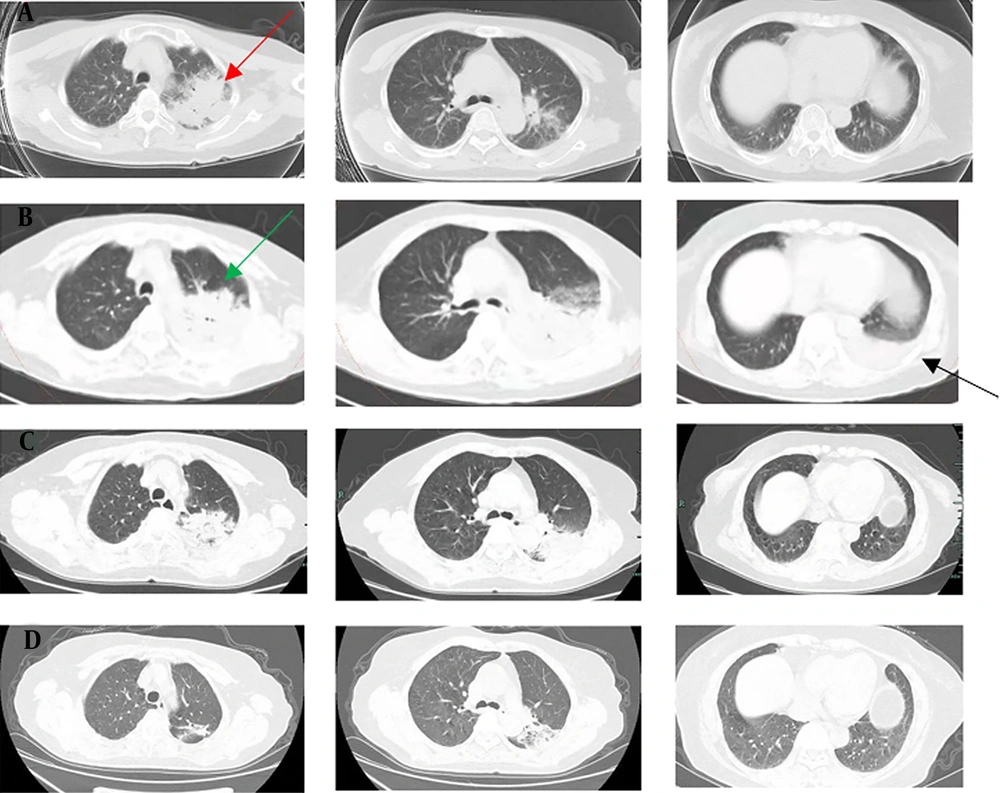

A, chest CT scan (November 20, 2021) indicated extensive inflammatory lesion with partial consolidation (red arrow) in the upper left lung; B, Enhanced pulmonary artery CT scan (November 24, 2021) indicated a local suspicious embolism in the right lower pulmonary artery, and consolidation progressed significantly in the left lung (green arrow) with left pleural effusion (black arrow); C, CT re-examination (November 30, 2021) showed that the lesions were obviously absorbed and pleural effusion disappeared; D, CT re-examination (December 25, 2021) showed further improvement.

Since the onset, the D-dimer remained at a high level, and relevant examinations were arranged. Enhanced pulmonary artery CT scan on day 3 indicated a local suspicious embolism in the right lower pulmonary artery, and consolidation progressed significantly in the left lung with left pleural effusion (Figure 2B). Therefore, low molecular weight heparin (LMWH) (4000 IU, every 12 hours, subcutaneous injection) was administrated. No other arteriovenous thrombosis was observed in the blood vessels, and there was no abnormality in cardiac ultrasound. Chest CT reexamination on day 9 showed that the lesions were absorbed, and the pleural effusion disappeared (Figure 2C). The symptoms of shortness of breath and cough were alleviated, and she was discharged on the 11th day without obvious complaint. The patient continued to receive treatment (doxycycline, 100 mg, every 12 hours, for 10 more days; rivaroxaban, 20 mg per day, at least 3 months). There was a further improvement in imaging (Figure 2D), and the case is being followed up on at present.

Although it is difficult to distinguish psittacosis pneumonia from those of other types of CAP by clinical manifestations and routine laboratory tests, they still show specificity for atypical pneumonia in radiology. Chest CT scans usually show different degrees of exudation and consolidation. Most of them are unilateral and single lobe consolidation; the second is unilateral multilobed consolidation and bilateral multilobed consolidation. The extent of consolidation is closely related to the severity of the infection. Patients with multilobed consolidation have a higher risk of respiratory failure. Consolidation is mainly in the lower lobe. Hilar lymph node enlargement or pleural effusion is rare. However, it is still difficult to distinguish it from Legionella pneumonia based on the above-mentioned characteristics. In this case, chest CT showed extensive multilobar pneumonia with pleural effusion but not bilateral, which was by severe cases but no need for ventilation, partly due to the timely diagnosis and treatment.